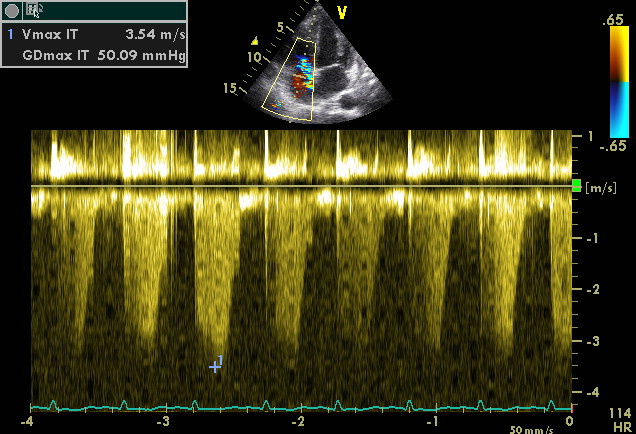

Enregistrement de la vitesse maximale de régurgitation d'un flux d'insuffisance tricuspidienne en Doppler continu. Sous contrôle bidimentionnel, le "tir" Doppler est dirigé selon l'axe des cavités droites